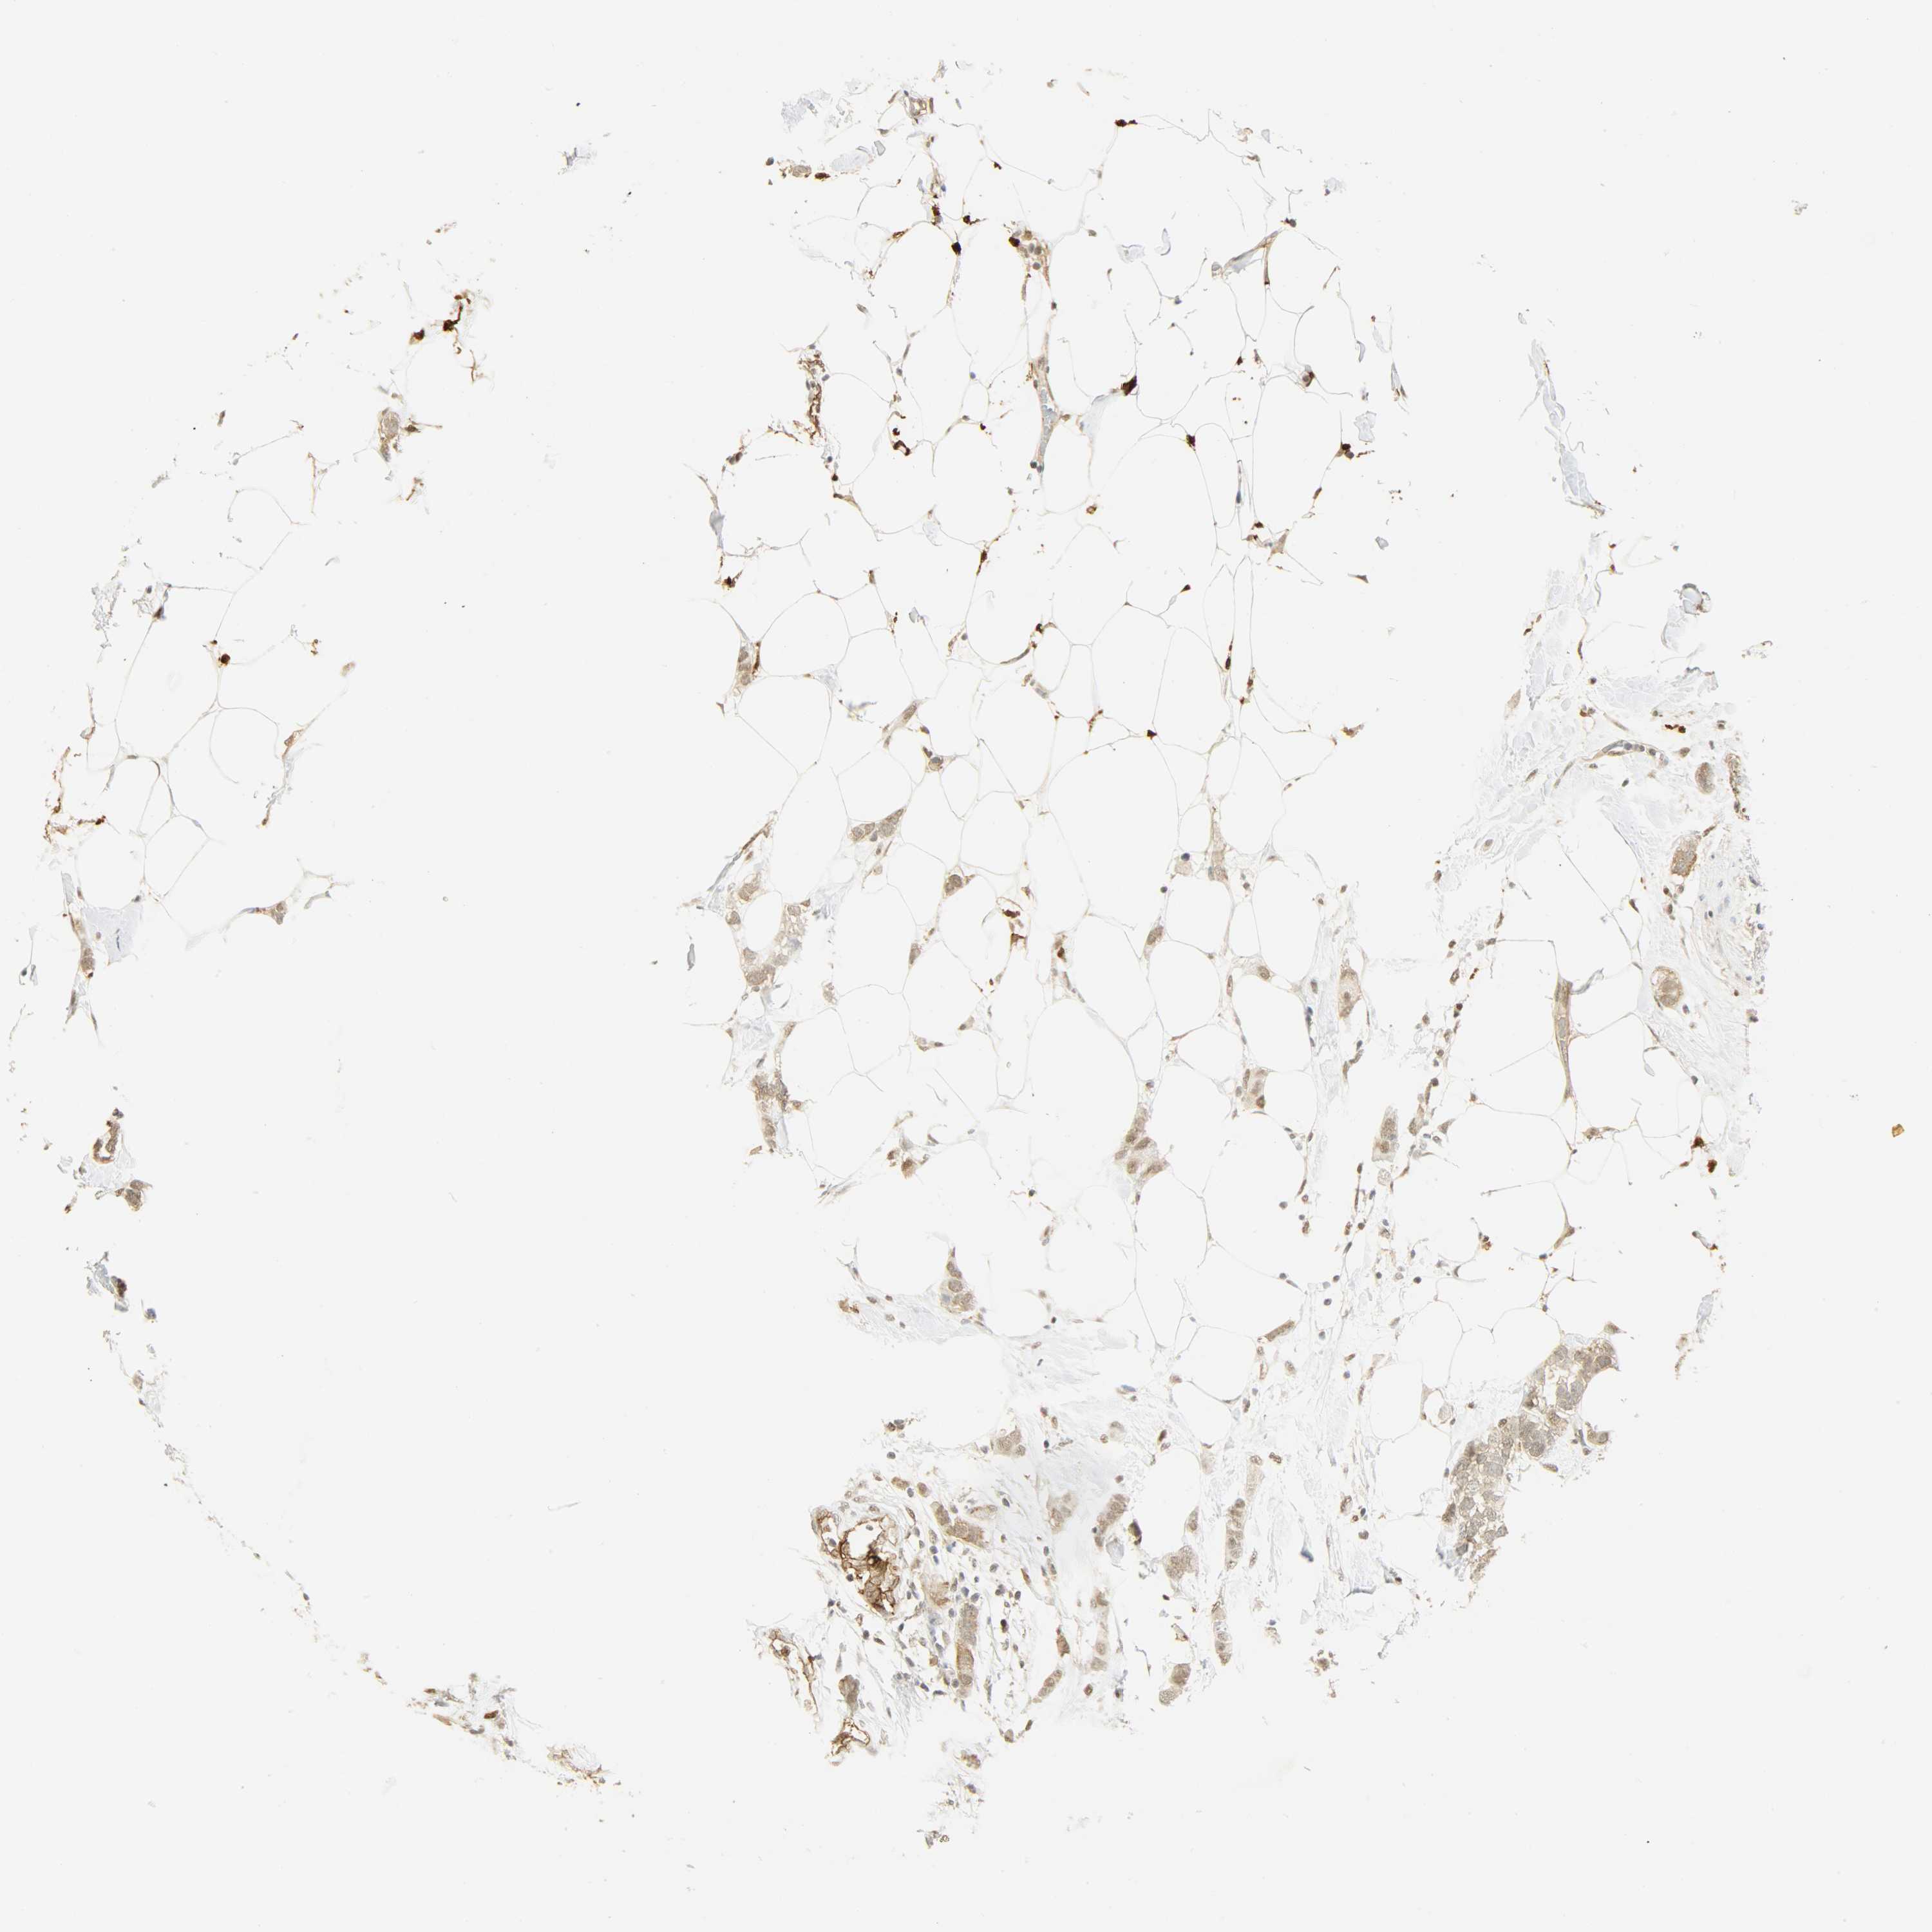

BRCA TCGA BRCA VALIDATION PROTEIN EXPRESSION

ANTIBODIES

AND

VALIDATION